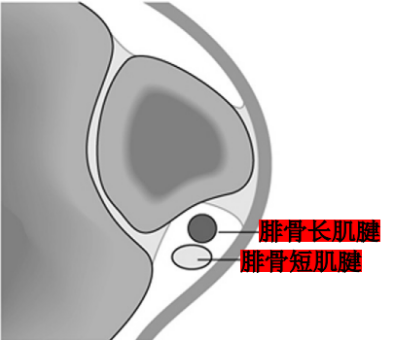

Raikin等学者提出将腓骨沟内腱鞘内半脱位不伴有腓骨上支持带损伤划为腓骨脱位的亚系。这些腱鞘内半脱位共有两型:

A型:腓骨肌腱无撕裂,肌腱暂时换位;

B型:腓骨短肌存在纵向撕裂,腓骨长肌腱自撕裂处半脱位。